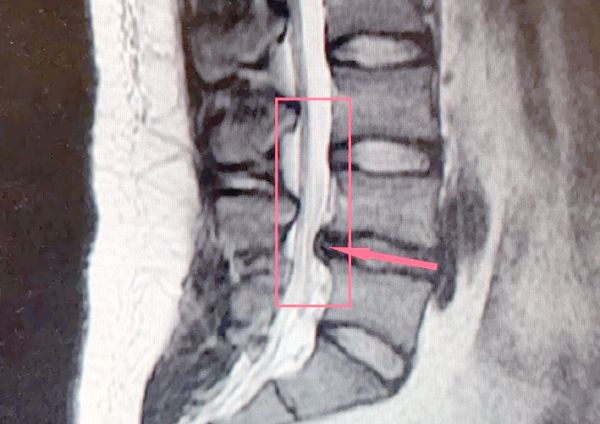

脊柱的生理曲度呈现一种凸凹结合的形态,其中颈椎和腰椎具有向前的生理前凸,而胸椎和骶尾椎则形成向后的生理后凸。若我们过度地抬头挺胸,这将会加大颈椎的前凸曲度,从而增加颈椎所承受的负荷。同时,胸椎原本的自然后凸曲度若被人为地过度挺直,不仅会加重胸椎的负担,还会因脊柱的整体性特点,导致腰椎代偿性地增大前凸角度,进而提升腰椎间盘所面临的压力。

这样,整个脊柱都会处于一个不正确的力线位置,导致相关的椎间盘、韧带和肌肉出现疼痛和慢性疾病。过度挺胸还会使肋骨外翻,从而影响呼吸的辅助肌群——肋间外肌和肋间内肌的收缩,进而损害呼吸功能。

当我们坐下时,臀部下方的骨性突起即为坐骨结节。为了避免“葛优躺”式的坐姿,将压力全部集中在尾椎骨上,导致骨盆后倾、腰椎曲度变直,甚至可能引发腰椎间盘突出,我们应当时刻保持双侧对称承重,避免跷二郎腿或身体偏向一侧,以防骨盆侧翻和脊柱侧弯。同时,确保臀部和背部都能得到椅子的有效支撑。腰部不应悬空,背部要挺直但不过度僵硬,可略向后倾斜,以保持腰椎和胸椎的自然曲度。此外,微微收腹有助于保持前后肌肉的平衡,使骨盆更加稳定。